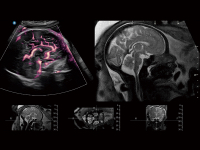

支持申請(qǐng)、預(yù)約、會(huì)診指導(dǎo)等會(huì)診流程管理,可實(shí)現(xiàn)遠(yuǎn)程終端音視頻互聯(lián),遠(yuǎn)程控制,支持多端互聯(lián),同步視頻具備高清、高幀率流暢畫(huà)面,幫助遠(yuǎn)地醫(yī)生和專(zhuān)家交流診斷結(jié)果

提供解剖示意圖、標(biāo)準(zhǔn)超聲圖像、掃查手法圖和操作者實(shí)時(shí)檢查圖像,指導(dǎo)操作者進(jìn)行標(biāo)準(zhǔn)切面的正確掃查。